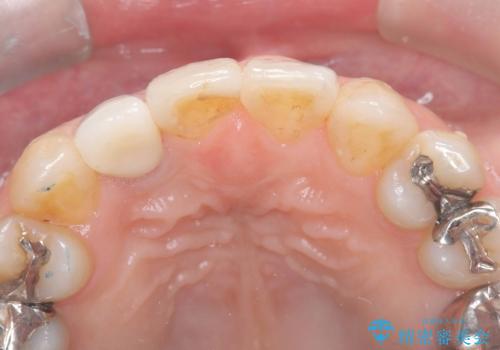

- 「前歯の見た目が気になる」を主訴に来院された患者様です。

失活歯による歯の変色とCR(コンポジットレジン)の劣化による審美不良でした。

オールセラミッククラウンで治療し見た目の改善を行いました。

まず劣化したCRと虫歯を除去した後、仮歯に置き換えました。歯のマージンラインを綺麗に削り光沢が出るまで研磨した後にオールセラミッククラウンの型取りを行っています。